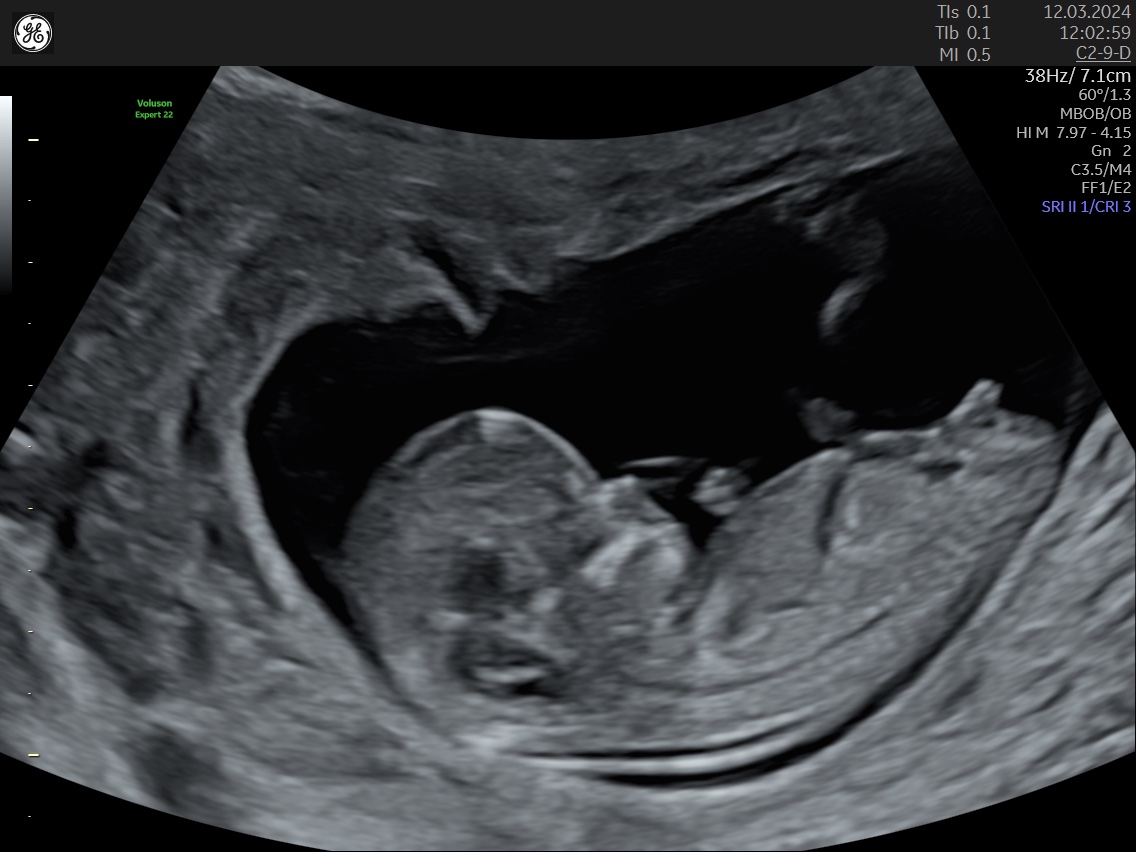

Lékař na screeningu mi odpověděl jen, že v tomto týdnu je pohlaví ještě nejisté (13. tt). Je mi jasné, že to není 100%, jen jsem zvědavá.

pohlaví z vyšetření na 1. screeningu nelze určit.